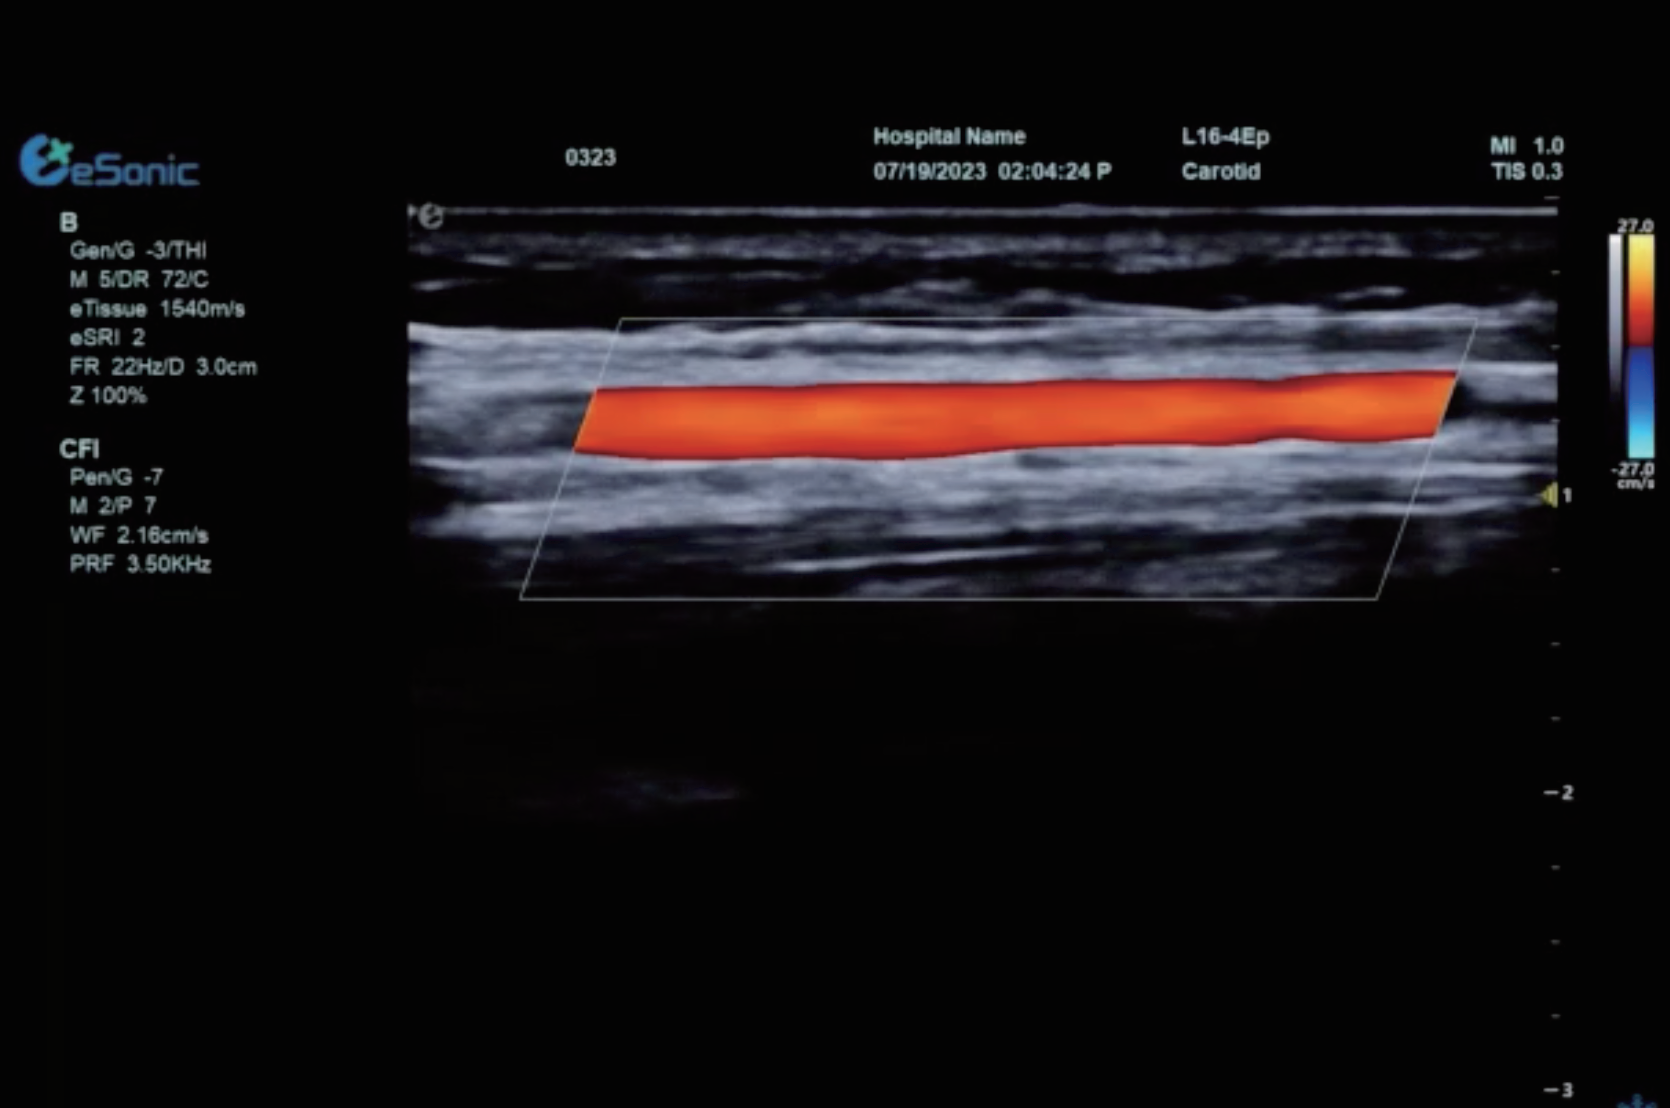

平面波超微细血流显像

彩色多普勒成像、3D壁滤波原理

血流敏感度明显提升,分辨率达微米级别

支持灰阶和微血流量同步测量、可测极低速血流的速度

多种模式,多数据定量评估。

74f501571ed455f9a4eebb1b8e37b73.png